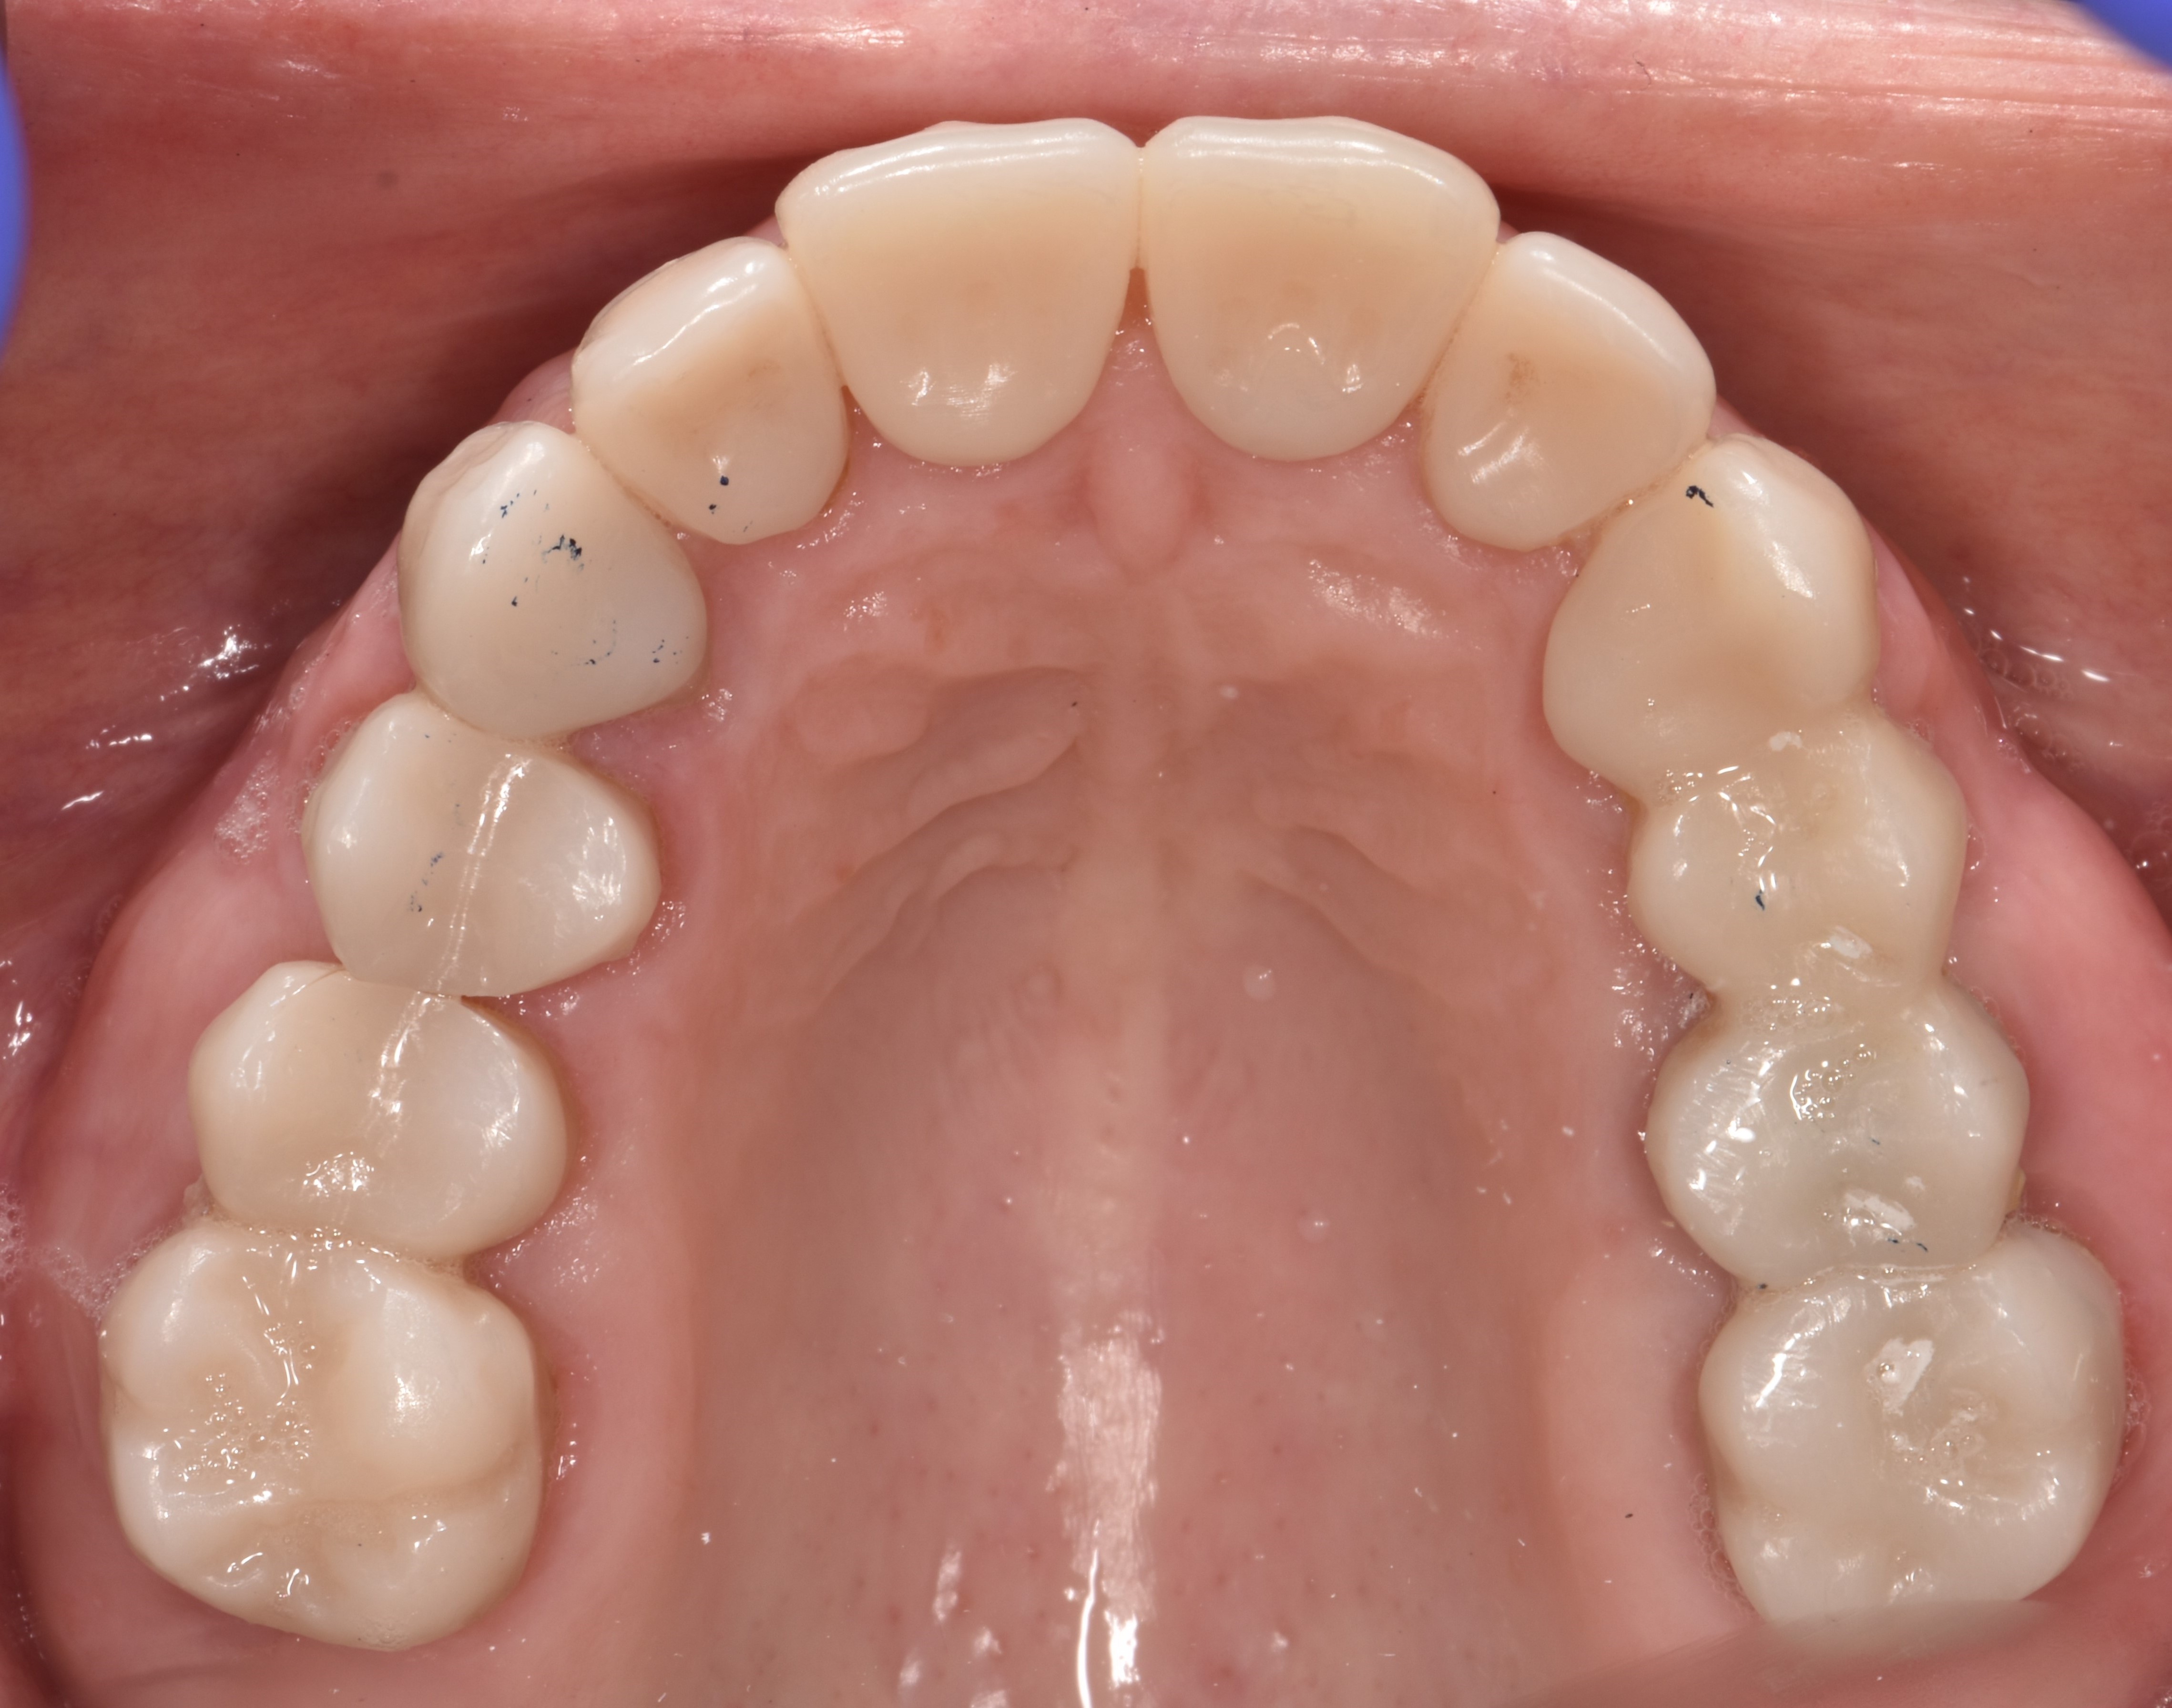

After the restorations were milled, they were sintered and polished for final effect. It was decided that these restorations should not be glazed to avoid the added abrasivity that accompanies this finish to the restoration.22 The patient was then scheduled for temporary crown removal. The final crowns were fitted on the prepared teeth, and the contacts adjusted. The patient reported that she was pleased with the feel and esthetics of the restorations, and the restorations were cemented (Figure 14 through Figure 19).

Fig. 14

Fig. 15

Fig. 16

Fig. 17

Fig. 18

Fig. 19